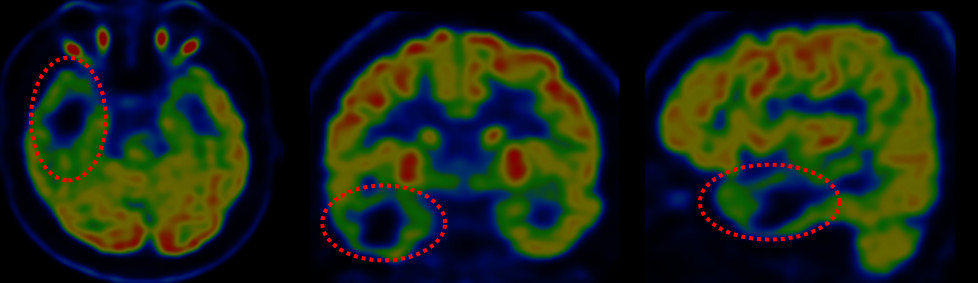

图6. 头颅PET提示右侧颞叶(AOS前)、颞叶内侧结构、岛前,左侧颞叶内侧结构低代谢。

男性患者,29岁,10首发,癫痫病史19年,十年前曾在外院行右侧颅内电极置入,后因无法定位癫痫病灶,拔出电极未手术,行右侧颞区γ刀治疗一次。入院前发作形式:先兆(难以描述的感觉,之后有凄凉感)→双手重复动作→左上肢屈曲上抬,左手兰花指样后握拳,右手摸索拍打,行为异常(四处乱走),每次1分钟,1次/周。头皮脑电图癫痫放电主要集中在右侧半球,颞区著。头部CT右侧颞叶有低密度改变,周围有散在钙化,头部MRI右侧颞前叶及颞叶内侧结构有异常信号,PET-CT提示右侧颞前叶、内侧结构、岛叶有低代谢。根据术前发作临床症状学、脑电图、影像学、功能影像学结果,考虑右侧边缘系统为致痫病变可能,颞叶内侧结构为主,对侧海马需鉴别,需要通过立体定向脑电图确认致痫区及其范围。用ROSA做了右侧颞区为主的双侧颅内电极置入。颅内电极监测结果发作间期癫痫放电和发作期起源主要在右侧颞叶内侧结构(右侧海马杏仁核),结合临床症状学及影像学、功能影像及颅内电极监测的结果,我们设计了右侧颞前叶及杏仁核、海马全段、岛叶前下部的切除方案,手术过程顺利,术后随访一年无发作及先兆。该患者10年前外院做过一次颅内电极置入及伽马刀治疗,对我们影像学的阅读增加了一些干扰因素,患者术后病理为海绵状血管瘤,按照国际抗癫痫联盟2011年的癫痫病理分类应该属于FCDⅢC型,病变核心区周围的脑皮层可能有发育异常,我们没有分区域做病理检查,只有对病变的核心区域做了病理检查。该患者影像学异常主要集中在颞前叶,患者发作的临床症状学主要边缘系统(颞叶内侧结构)的发作,最后颅内电极也证实了,发作间期异常癫痫放电及发作期起源均来自于颞叶内侧结构,所以我们最后做了颞前叶及内侧结构的切除,如果单看影像学只切除颞前叶病变效果肯定不好。颅内电极在该患者治疗中,为我们验证了致痫区及决定切除范围起到了很重要的作用。